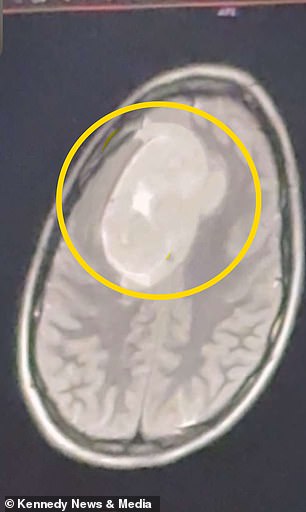

The dismissal lingered in her mind, but Keating pushed forward, determined to find answers. During her Christmas break, she returned home and sought a second opinion. This time, the doctor ordered an MRI scan, a decision that would change her life forever. The results, revealed in January 2026, showed a two-inch tumor in her left frontal cortex — roughly the size of a tennis ball. 'I was stunned,' Keating says. 'That was the last thing I would have expected.' The tumor was benign, but its location posed a serious threat. Pressing against the frontal lobe, which controls executive function, motor skills, and language, it could have led to severe cognitive decline, personality shifts, or even paralysis if left untreated.